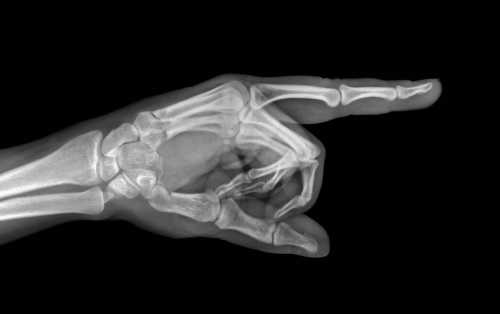

Укладки при выполнении снимков. Снимки пальцев производят в прямой и боковой проекциях.

Укладки при рентгенографии I пальца и II —V пальцев имеют ряд отличий.

Снимок I пальцакисти в прямой тыльной проекции.

I палец прилежит к кассете тыльной поверхностью. Кисть и предплечье максимально ротированы кнутри. Для фиксации кисти в заданном положении больной удерживает ее здоровой рукой.

Используют кассету размером 13X1 8 см, перекрывая ее поперек листом просвинцованной резины.

Пучок рентгеновского излучения направляют отвесно на проекцию пястно-фалангового сустава (рис. 373).

На рентгенограмме видны фаланги и частично I пястная кость, их медиальные и латеральные поверхности, рентгеновские суставные щели пястно-фалангового и межфалангового суставов, бугристость дистальной фаланги (рис. 374).